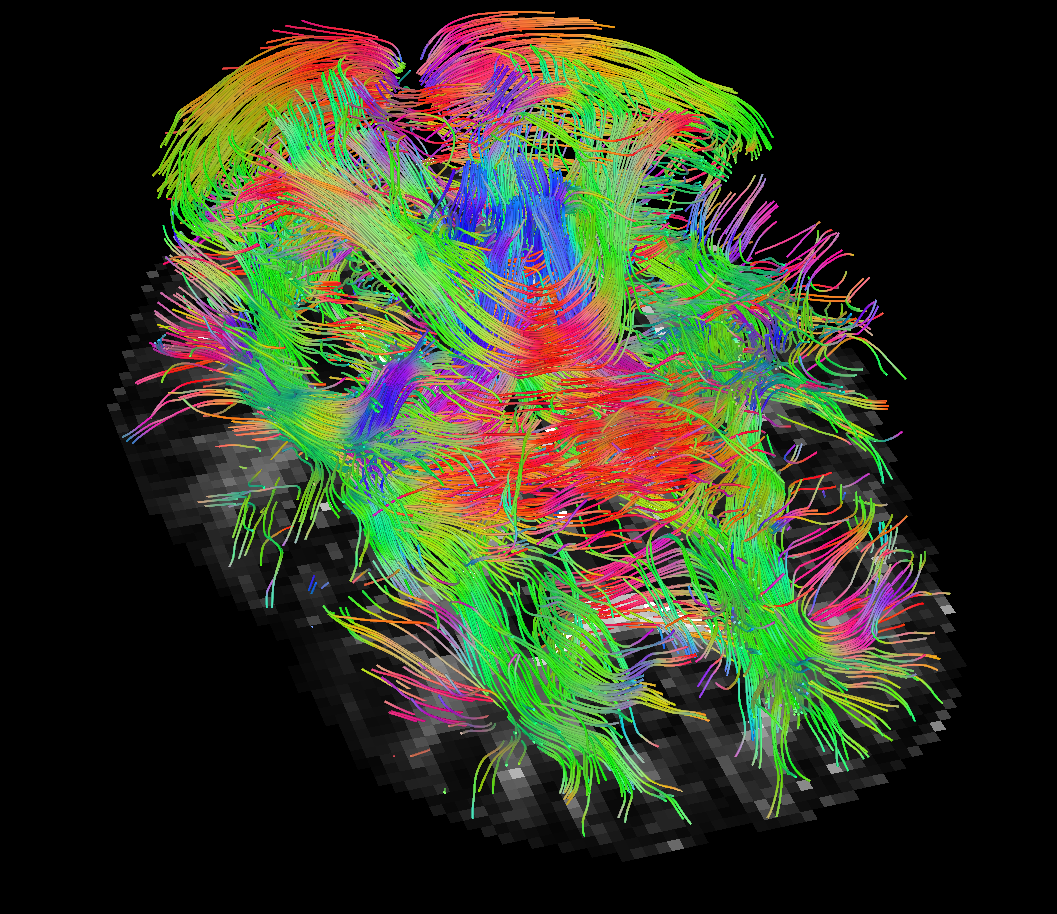

It shall also be investigated whether the error bounds approach needs to be combined with an alternative, novel, regulariser that would ameliorate the fractional anisotropy errors that the approach exhibits. It is important to note, however, that from the practical point of view, of using the reconstruction tensor field for basic tractography methods based solely on principal eigenvectors, these are not that critical. As pointed out by one of the reviewers, the situation could differ with more recent geodesic tractography methods [hao2011adaptive, schultz2014novel, fuster2016adjugate] employing the full tensor. We provide basic principal eigenvector tractography results for reference in Figure 9, without attempting to extensively interpret the results. It suffices to say that the results look comparable. With this in sight, the error bounds approach produces a very good reconstruction of the direction of the principal eigenvectors, although we saw some problems with the magnitude within the corpus callosum.